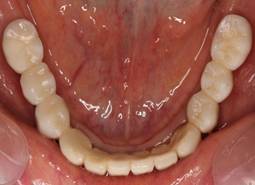

術後。上部構造はハイブリッドレジンです。しっかり嚙めるようになり喜んでいただきました。

上顎

下顎

上部構造装着後6年。ハイブリッドレジンを使用したため、少し艶がなくなってきました。上部構造の材料には金属、ハイブリッドレジン、セラミックなどがあります。セラミックはきれいですが欠けやすいため、最近はフルジルコニアを使っています。

上顎 少しすり減ってきました。

下顎。12か月に一度メインテナンスをしています。

インプラント装着後6年。順調に経過しています。12か月毎のメインテナンスをしています。